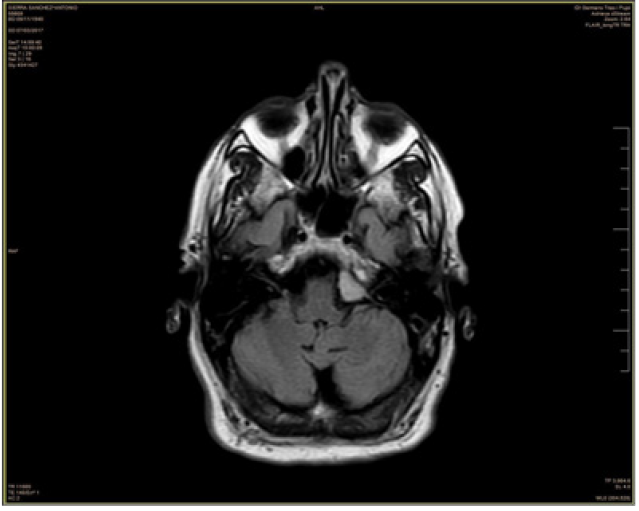

The MRI showed an extra-axial image in the posterior fossa, with a base of meningeal implantation in the left aspect of the clivus, sized 10 x 10 x 20 mm, with intense and homogeneous gadolinium uptake, and was insinuated to the entrance of the internal auditory canal without clear distortion of cranial nerves or evident mass effect on the protuberance. It was concluded that the lesion could correspond to the one mentioned in the PET-CT and radiologically it was consistent with meningioma (Figure 2.).

Figure 2. MRI shows an extra-axial image in the posterior fossa, with a meningeal implantation base on the left aspect of the clivus. It shows intense and homogeneous gadolinium uptake.

Figure 4. In MRI control, extra-axial lesion persisted. Regarding the previous study, its diameters had not changed, and the appearance of edema or other underlying bone involvement was not appreciated. No other extra-axial lesions or other relevant changes with respect to the previous study.